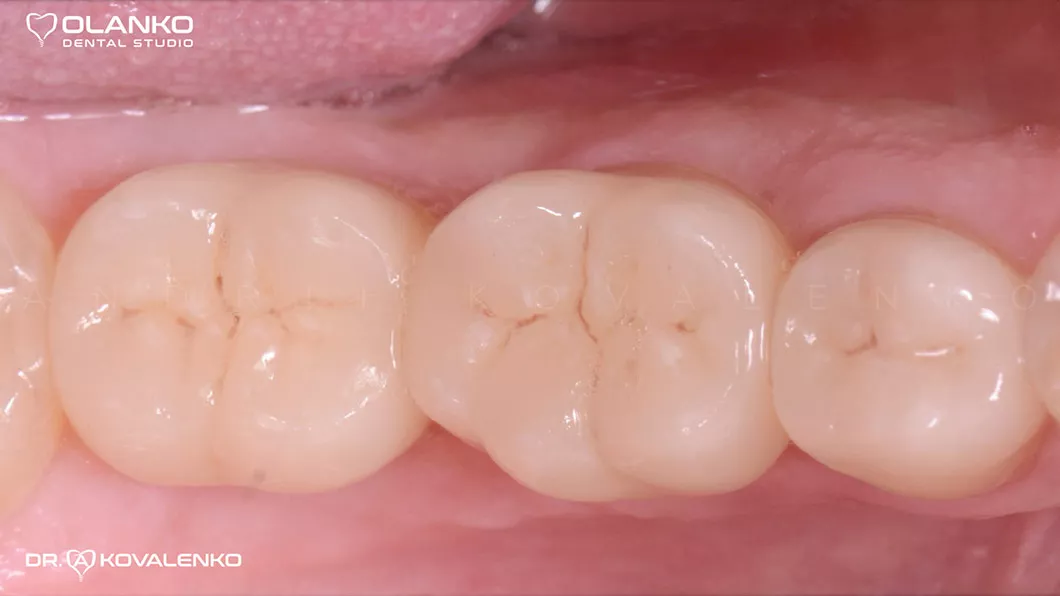

Готовые цельнокерамические коронки

Вид после фиксации коронок